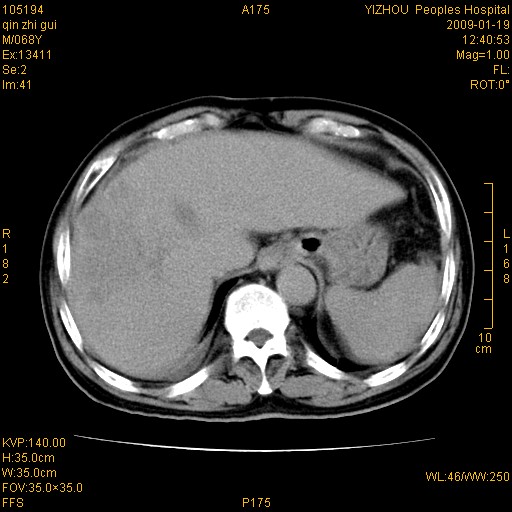

以下是引用随光逐影在2009-1-21 16:11:00的发言:[br]1)考虑肝右叶肝癌并肝静脉及门静脉瘤栓形成。2)肝硬化,少量腹水。3)胆囊炎。4)右侧少量胸腔积液。

病灶外缘凹凸不平,平扫低密度,增强动脉期有强化,门脉早显,静脉期及延期呈延迟强化,结合病史考虑右肝前叶巨块型肝癌可能性大,强化表现不除外胆管细胞癌